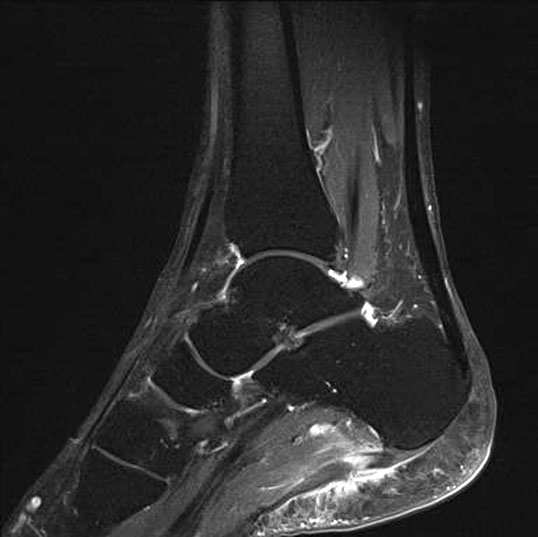

Hier befindet sich ca. 3-5 cm proximal des Tuber calcanei ein als „kritische Zone“ benannter Bezirk, der durch eine ungünstige arterielle Blutzufuhr gekennzeichnet ist (letzte Wiese). Hier finden sich häufig spindelförmige Schwellungen, die bei MRT-Diagnostik nicht selten partielle Nekrosen und Partialrupturen der Achillessehne aufweisen (Abb. 14).

Unabhängig davon können insbesondere chronische Insertionstendinosen der Achillessehne von Partialrupturen (Abb. 15) und erosiven Läsionen des dorsalen Fersenbeines begleitet sein.

Die sonographische Diagnostik eignet sich primär zur Erkennung schmerzhafter Prozesse im Verlauf der Achillessehne und kann bei Bedarf durch Röntgen bzw. MRT ergänzt werden. Besonders bei längeren Verläufen und kräftigen spindelförmigen Schwellungen (>9mm, Normwert <5mm) im Bereich der kritischen Zone sollte ein MRT zum Ausschluss von Nekrosezonen und Partialrupturen vor Therapiebeginn veranlasst werden. Die sonographisch leicht zu erfassende Veränderung der Sehnendicke im mittleren Sehnenanteil ist ein guter Indikator für die Schwere der Erkrankung und die Beurteilung des Behandlungsverlaufes. Die sichtbaren Veränderungen am distalen knöchernen Ansatz der Sehne sind diskreter.

Insbesondere bei größeren Partialrupturen (Abb. 14) sollten operative Verfahren erörtert werden. Kleinere Partialrupturen sind der ESWT gut zugänglich, wie die beiden nachfolgenden Beispiele zeigen: